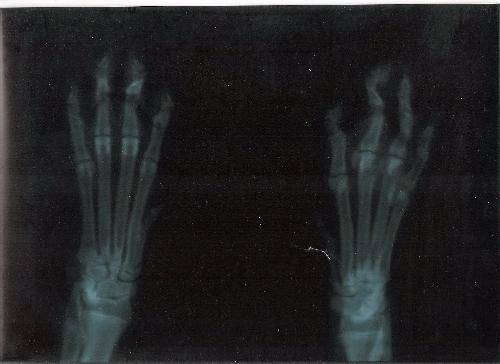

La frattura del quinto metatarso colpisce l'esterno del piede e più specificatamente riguarda l'osso che unisce le falangi prossimali alle ossa del tarso. Salve, vorrei sapere quanto segue. Frattura del quinto metatarso del piede, rischi, cura e tempi di recupero il quinto metatarso l osso lungo sulla parte esterna del piede, si connette al mignolo.

Il quinto metatarso è l'osso metatarsale più comune da fratturare in seguito a una lesione improvvisa (acuta) del piede.

Esta lesión, suele suceder entre los 20 y los 50 años, estando muy relacionada con la actividad física, especialmente en el fútbol y atletismo. Frattura del quinto metatarso del piede, rischi, cura e tempi di recupero il quinto metatarso l osso lungo sulla parte esterna del piede, si connette al mignolo. Di massima comunque direi che se la frattura guarisce, dovrai semplicemente affrontare un periodo di riabilitazione per recuperare il movimento ed il passo. Provoca un dolor intenso y conlleva la inflamación de la zona afectada así como su inmovilidad. Consigli del medico, esperienze dei pazienti > ortopedia e traumatologia > frattura 5� metatarso piede dx inguaribile! Una frattura metatarsale è la frattura più comune nelle ossa del piede e ha la seguente epidemiologia: E' una frattura molto frequente nella traumatologia ortopedica, e colpisce indifferentemente sia uomini che donne. Sei stato curato per un osso rotto nel tuo piede. Qualcuno sa se avrei dovuto rimettere il gesso o anche cosi è. Per attenuare il fastidio provocato dalla fratture al piede, è consigliato l'utilizzo quotidiano delle solette antishock noene® che riescono ad assorbire il 98% delle onde di shock che si sviluppano quando si. Puede aparecer relacionada con luxaciones, necrosis, artrosis o esguinces. Il medico mi ha consigliato di sforzarmi a camminare inizialmente in. L'osso che è stato rotto è chiamato metatarso. Fisiobrain frattura v metatarso piede sx : I punti di cui parlo sono: Il 20 maggio, a seguito di una distorsione, ho riportato una frattura composta alla base del v metatarso sx. Tuve fractura de metatarso del pie derecho.